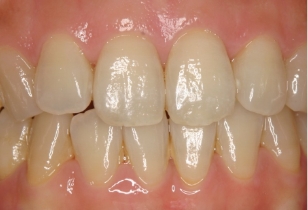

伊藤矯正歯科医院での安定した症例

これに対し伊藤矯正歯科医院では、抜歯を伴う矯正を行ったのちに何も装置を使用しなくて何年か経過しても、かなり安定している症例をみることが多くありました。(「安定調査症例1~4」と当HPの症例集ページ「叢生第3,4症例」をご覧下さい。)そこで治療が終わって数年経過した時点で、資料採得のできた14症例について歯並びの変化を観察しました。

これによると当院の治療後の歯並びの変化は、従来の矯正に比べ変化が非常に少ない事が分ります。つまり当院の矯正治療は、従来の矯正治療に比べ大変に安定していることが分かります。

このように当院の矯正治療の術後経過は、従来の矯正に比べ安定していることが分かります。